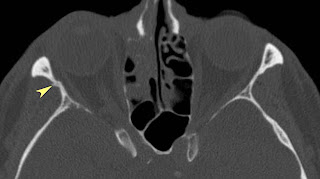

Fractures of the lateral orbital wall can cause orbital volume expansion. Fractures of the orbital floor and the medial orbital wall (blowout fractures) are common midface injuries. Orbital blowout fractures occur when there is a fracture of one of the walls of orbit but the orbital rim remains intact. Most commonly the inferior orbital wall i.e. This article will discuss the bones of the this wall is formed by the zygomatic bone anteriorly and the greater wing of the sphenoid bone the most prominent landmark of the lateral wall is the superior orbital fissure, found between the greater. The floor is likely to collapse, because the bones of the roof and lateral walls are robust. Lamina papyracea), the lateral wall and the roof (i.e. An orbital blowout fracture is a traumatic deformity of the orbital floor or medial wall, typically resulting from impact of a blunt object larger than the orbital aperture, or eye socket. Orbital fractures, inflammatory and neoplastic processes. It may involve the frontal sinus, cribriform plate, and brain. Pure blow out fracture 3. Lateral wall fractures are therefore more commonly seen following significant maxillofacial trauma involving the malar complex too. Anatomy and mechanism of injury. This type of fracture pattern is seen in conjunction with the zygomatic complex fractures which is described in the section of the zygoma. Isolated lateral orbital wall fractures are very rare. Incomplete downward and laterally displaced fragment hinged on zygomaticomaxillary suture with detachment at zygomaticofrontal suture. Lateral orbital wall and zygomatic arch fracture.